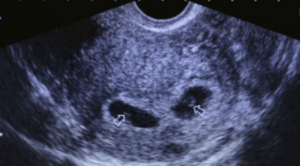

Беременность двойней определяется по прослушиванию двух сердечных ритмов, наличию двух полых оболочек с околоплодными водами (плодный пузырь), и двух эмбриональных органов (плацента или «детское место»). Хорион – источник развития плаценты и амнион – околоплодный пузырь, дают название типам развития близнецов в утробе.

Каждый эмбрион располагается в персональном околоплодном пузыре и имеет своё «детское место». При таком типе развития, близнецы, чаще всего, бывают разнояйцевые, и определить двойню на ультразвуковой диагностике возможно уже на пятой неделе вынашивания детей, то есть при первом проведенном женщине скрининге.

При данном типе беременности наличие двух детей можно заметить не ранее, чем на 9-11 неделе, поскольку дети находятся в разных амниотических пузырях, которые расположены в одном «детском месте».

Схематический пример двойни первого (монохорильная диамниотическая) и второго (дихориальная диамниотическая) типа

Такую однояйцовую двойню УЗИ, как правило, не может показать на первом проведенном женщине скрининге. Эмбрионы соединены общей околоплодной оболочкой и расположены в одной плаценте. Дети данного типа вынашиваются тяжело, нередко с осложнениями.